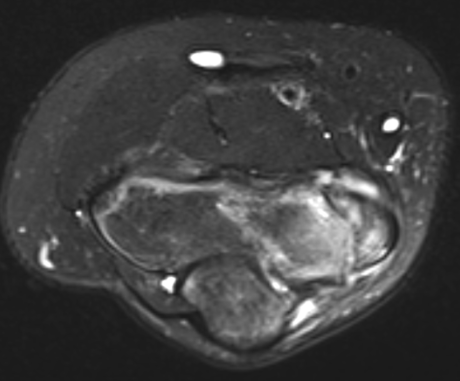

MRI

Edema around medial epicondyle

UCL injuries